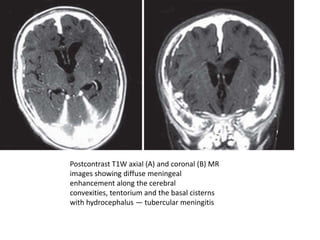

Postcontrast T1W axial (A) and coronal (B) MR

images showing diffuse meningeal

enhancement along the cerebral

convexities, tentorium and the basal cisterns

with hydrocephalus — tubercular meningitis

• Postcontrast T1-weighted MR images show

diffuse meningeal enhancement, mainly at the

basal cisterns and the sylvian fissures